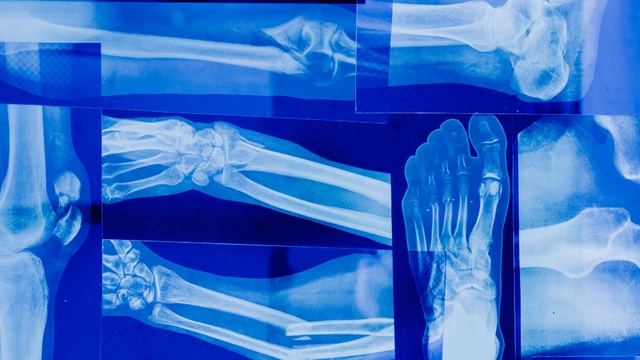

Phân thùy phổi trên phim X-quang là yếu tố quan trọng trong chẩn đoán và điều trị các bệnh lý phổi. Việc hiểu và phân thùy phổi trên phim X-quang giúp bác sĩ chẩn đoán chính xác và lập kế hoạch điều trị hiệu quả. Bài viết này cung cấp hướng dẫn chi tiết về phân thùy phổi trên phim X-quang, dựa trên các nguồn tài liệu khoa học uy tín.

Mỏm trâm là một xương sụn hình trụ, dài nằm trên xương thái dương mà ít người biết đến. Hãy cùng tìm hiểu xem dài mỏm trâm biểu hiện thành những triệu chứng nào qua bài viết sau.